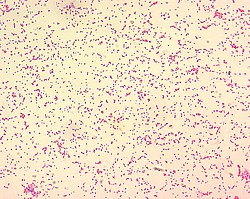

| Brucella spp. are gram-negative in their staining morphology. Brucella spp. are poorly staining, small gram-negative coccobacilli (0.5-0.7 x 0.6-1.5 µm), and are seen mostly as single cells and appearing like "fine sand". | |